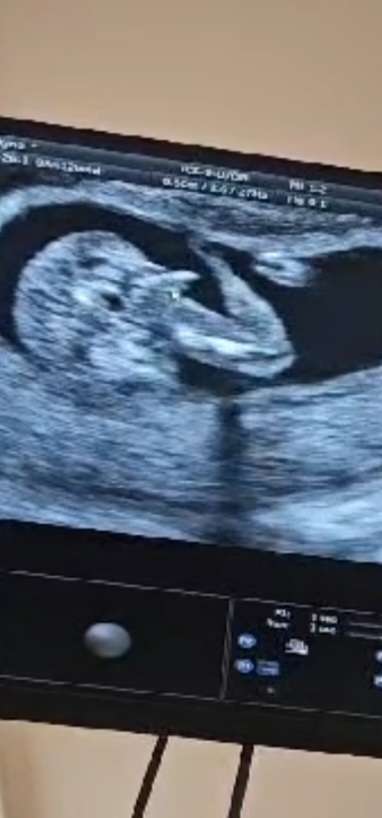

Robiłam z krwi badania genetyczne ale w poniedziałek to był 12+4 lekarz też na usg potwierdził chłopaka, bo jak mówi ,,wywalił sprzęt na widok" 😂 tu gdzie kursor myszki to siusiak

No on widział z każdej pozycji dziecko a w tej nocnikowej pokazał mi, że to meski wyrostek. Jako, że nagrywałam komórka badanie dla narzeczonego to się śmiał i mowil: Patrz tata jest siusiak:)